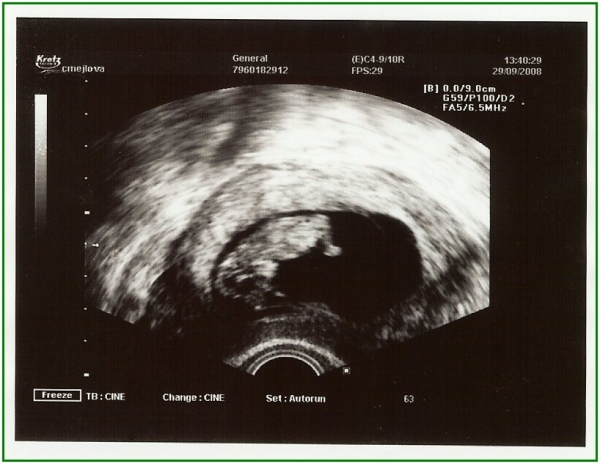

Pod pokličkou poprvé

Pod pokličkou podruhé

Už o mě vědí (8 týden) a klidně si jedou na rafty, blázni.